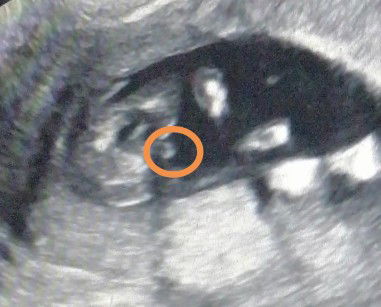

Gender

Boy po ba or girl?

I think baby boy po 😊

girl